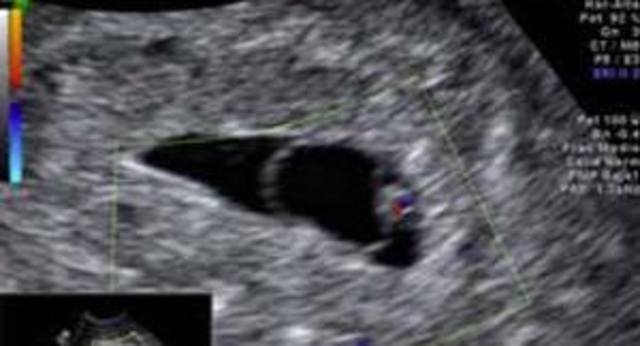

• Décima octava semana.

Décima octava semana.

El bebé mide entre 12,5 y 14 cm y pesa 150 gr

El corazón del feto esta dividido en cuatro cámaras (dos aurículas y dos ventrículos) y cuatro válvulas (tricúspide, mitral, aortica y pulmonar). Parte de la sangre de la aurícula derecha pasa directamente a la aurícula izquierda a través e un agujero llamado foramen oval evitando el paso de esa sangre a los pulmones los pies y las piernas están moldeados.